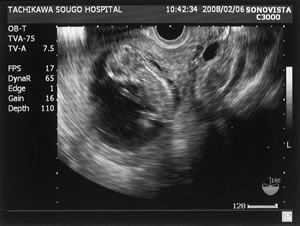

| 超音波検査の赤ちゃんの画像(12週) |

妊娠を疑ったら受診をして、正常妊娠かどうかの診断を受けましょう。まず尿検査をおこない、妊 娠性のホルモンが出ているかを確認します。陽性であれば超音波検査で、子宮の中に胎嚢(赤ちゃんが育つ部屋)があるか、胎嚢の大きさは最終月経から推定さ れる大きさと一致しているかどうかを見ます。